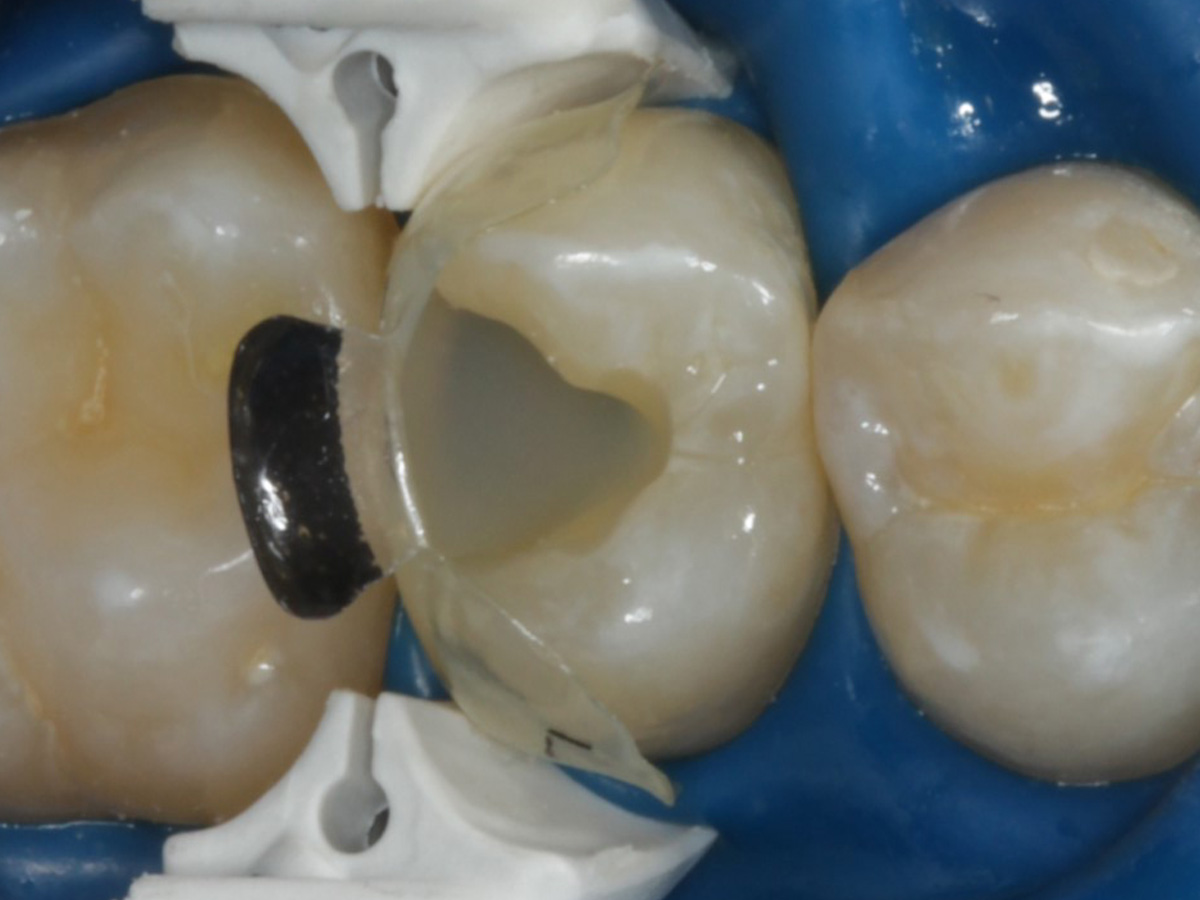

Abbildung 10

Nach Spray und Trocknung der Kavität: perfekte Adaptation der Matrize insbesondere tief subgingival